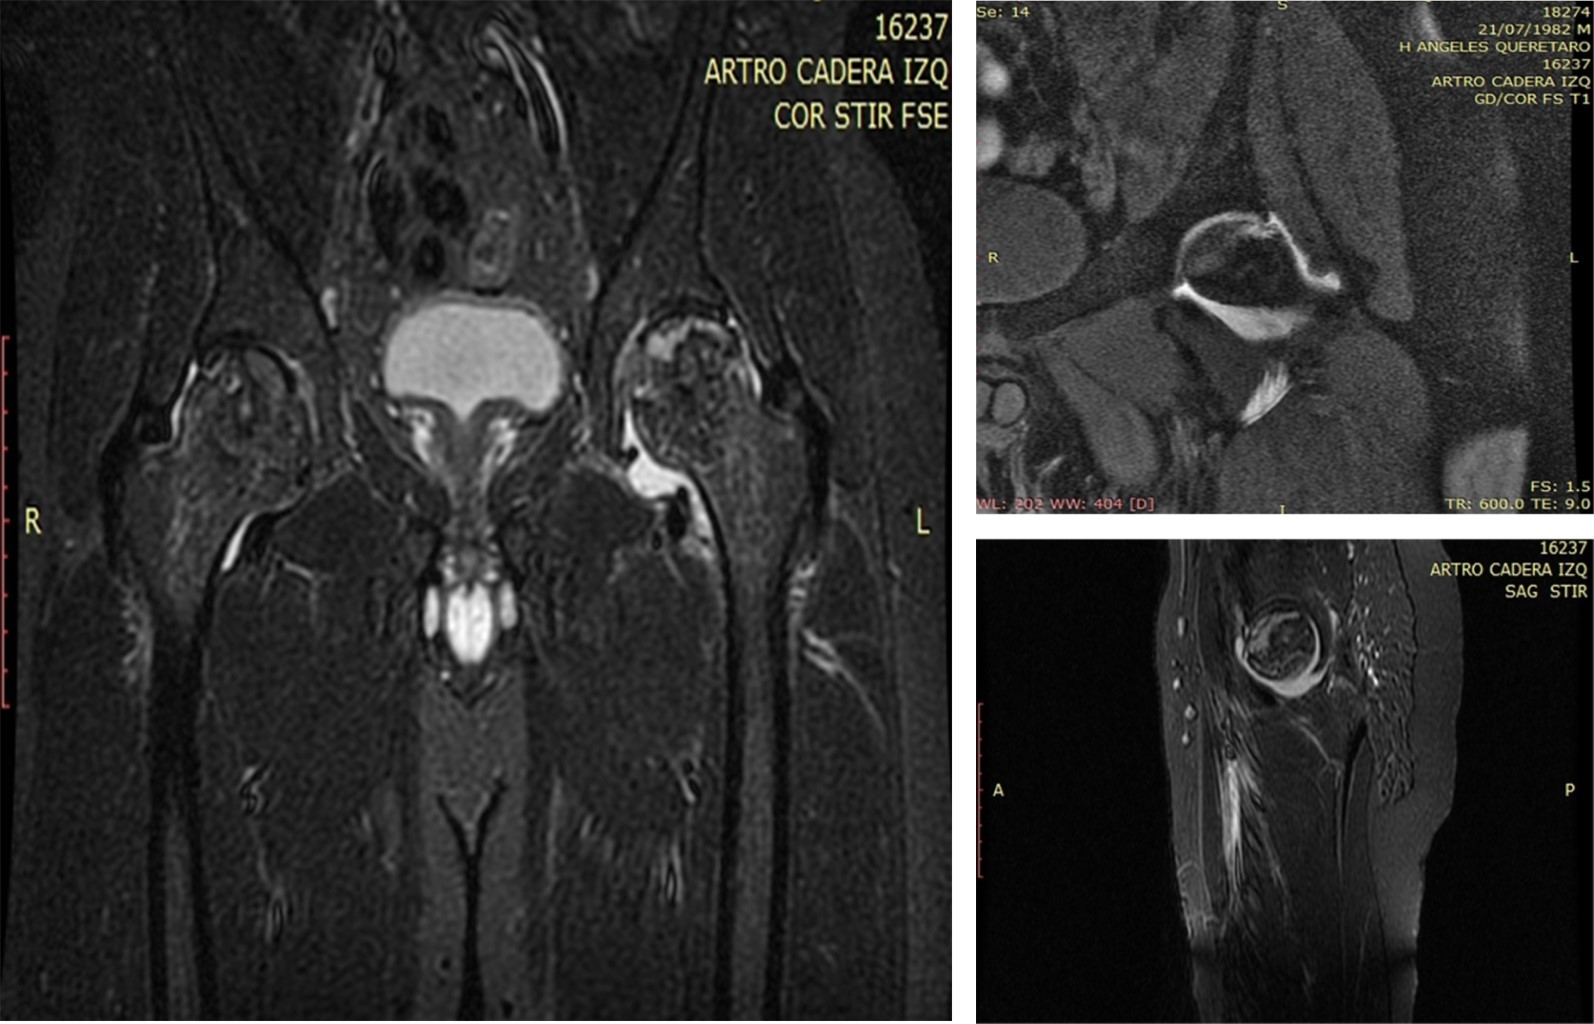

Figure 4